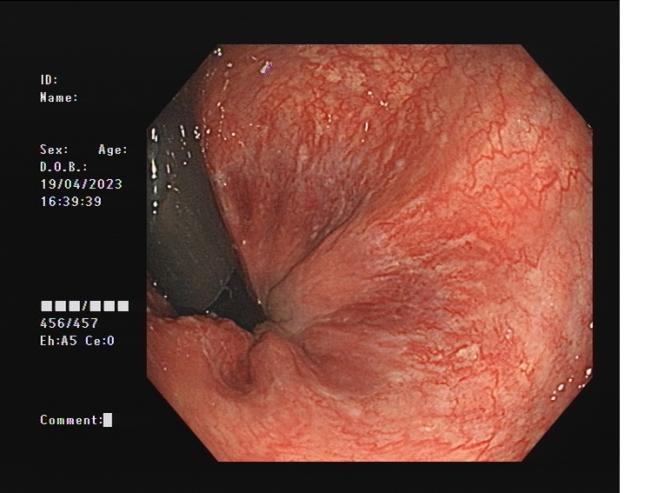

直腸側向發育性腫瘤 內鏡下黏膜下剝離術后創面

內鏡下黏膜剝離術(ESD):治療巨大平坦息肉,早期癌及癌前病變,黏膜下腫瘤等。